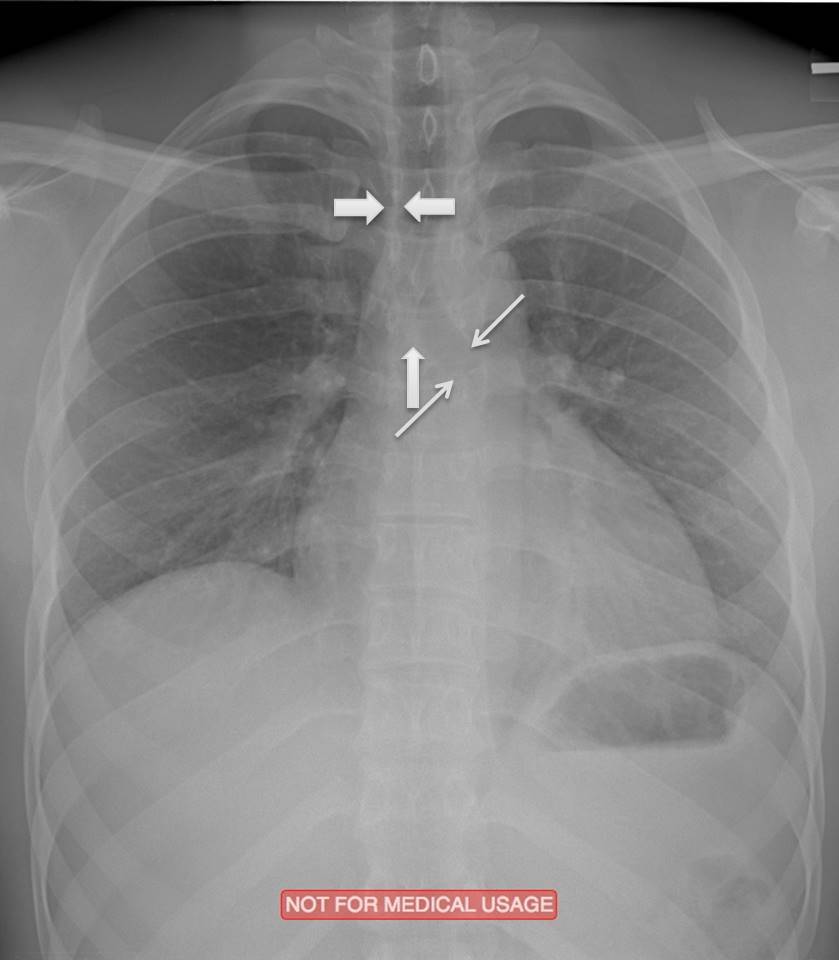

What structures are indicated by the arrows?

Right Paratracheal Stripe

Carina

Left Mainstem Bronchus